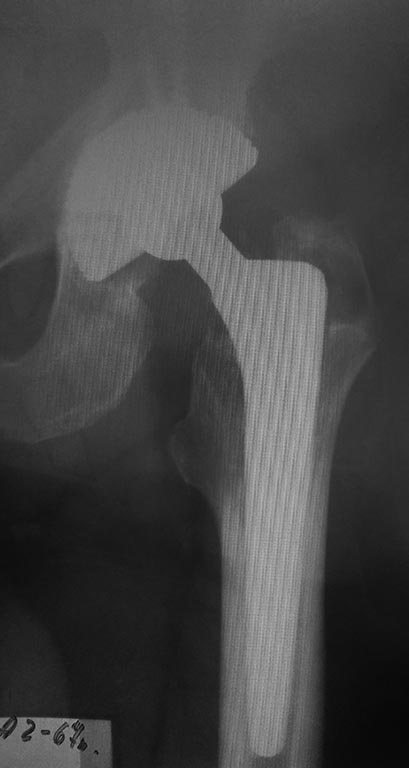

Р-грамма 2019 год

Децентрация головки эндопротеза в вертужной впадине? Доброго дня, уважаемые коллеги. В настоящее время на консервативном лечении находится пациент 1951 г.р., мужчина. В 2009 и 2010 гг.по поводу коксартроза выполнено тотальное эндопротезирование правого и левого тазобедренных суставов. В течение длительного времени беспокоит боль в левом тазобедренном суставе, периодически возникают эпизоды, которые пациент расценивает как подвывих, устраняет эти ощущения ротацией н/конечности. Рентгенограмм в момент "вывиха" не выполнялось. На контрольных рентгенограммах отмечается децентрация головки эндопротеза слева, смещение головки в краниальном направлении. Пациент консультирован в нашем ведущем учреждении, убедительных данных за нестабильность эндопротеза не выявлено, рекомендации- лечение консервативное. Однако, учитывая рентгенологическую картину, нельзя ли предположить износ полиэтилена? Каковы рекомендации в плане дальнейшей тактики?

Приблизил и обрезал отдельно ацетабулярный компонент. Видно, что головка не по центру ацетабулярного компонента, а смещена кверху